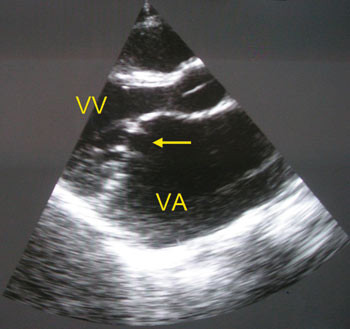

Mitralstenose, alene eller predominerende, foreligger hos ca. 40 % av pasienter med kronisk revmatisk hjertesykdom (fig 3 og 4). Konservativ medikamentell behandling er diuretika og betablokkere, mens ballongvalvuloplastikk av stenotisk klaff er den kirurgiske behandlingen (25). Mitralinsuffisiens ses ofte kombinert med stenose.